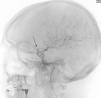

Más datosA 49-year-old woman suffered a first seizure episode. The brain CT scan (Fig. 1) revealed a giant aneurysm of the left internal carotid artery (ICA) with subtotal thrombosis (no CT-angio contrast uptake). Arteriography was decided (Fig. 2), showing a large left carotid-ophthalmic aneurysm, with a minimum patent portion (8 × 5 mm). The rest proved thrombotic. During arteriography, the patient developed hemiparesis and deviation of the vocal commissure, with arteriographic vasospasm that subsided with verapamil. Magnetic resonance imaging (Fig. 3) described the aneurysm with a left frontal parasellar location, measuring 4.2 × 3.9 × 3.6 cm, originating at the top of the left ICA and exerting a mass effect upon both anterior cerebral arteries and the left middle cerebral artery, as well as compression and right displacement of both frontal horns. The MR-angio study evidenced a 9-mm saccular dilatation in the supraclinoid portion of the left ICA, located within the lower third of the described lesion. A differential diagnosis with contained rupture of the aneurysm was considered. Surgery with clipping of the aneurysm was decided, with confirmation of its partial thrombosis and an intact capsule. The patient subsequently remained symptoms-free, with salt-wasting syndrome as the only posterior complication.